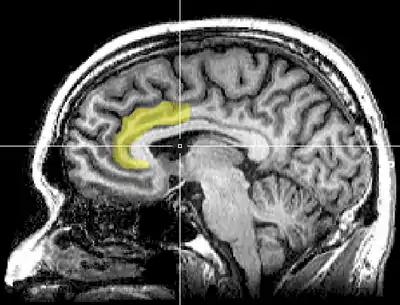

Brain imaging techniques including magnetic resonance imaging (MRI), functional magnetic resonance imaging (fMRI), and positron emission tomography (PET) have shown that there are two main areas in the brain that are involved in the processing of the Stroop task.[8][9] They are the anterior cingulate cortex, and the dorsolateral prefrontal cortex.[10] More specifically, while both are activated when resolving conflicts and catching errors, the dorsolateral prefrontal cortex assists in memory and other executive functions, while the anterior cingulate cortex is used to select an appropriate response and allocate attentional resources.[11]

The posterior dorsolateral prefrontal cortex creates the appropriate rules for the brain to accomplish the current goal.[11] For the Stroop effect, this involves activating the areas of the brain involved in color perception, but not those involved in word encoding.[12] It counteracts biases and irrelevant information, for instance, the fact that the semantic perception of the word is more striking than the color in which it is printed. Next, the mid-dorsolateral prefrontal cortex selects the representation that will fulfill the goal. The relevant information must be separated from irrelevant information in the task; thus, the focus is placed on the ink color and not the word.[11] Furthermore, research has suggested that left dorsolateral prefrontal cortex activation during a Stroop task is related to an individual's’ expectation regarding the conflicting nature of the upcoming trial, and not so much on the conflict itself. Conversely, the right dorsolateral prefrontal cortex aims to reduce the attentional conflict and is activated after the conflict is over.[10]

Moreover, the posterior dorsal anterior cingulate cortex is responsible for what decision is made (i.e. whether someone will say the written word or the ink color).[10] Following the response, the anterior dorsal anterior cingulate cortex is involved in response evaluation—deciding whether the answer is correct or incorrect. Activity in this region increases when the probability of an error is higher.[13]